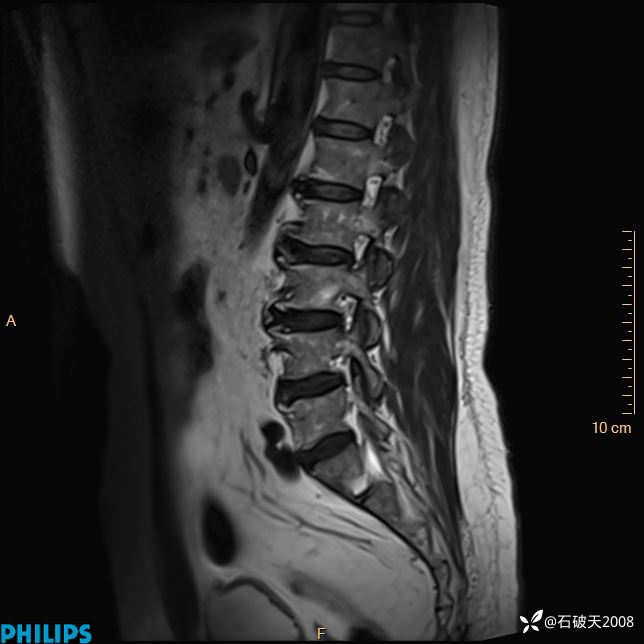

2023年3月份MRI影像

T1矢状位